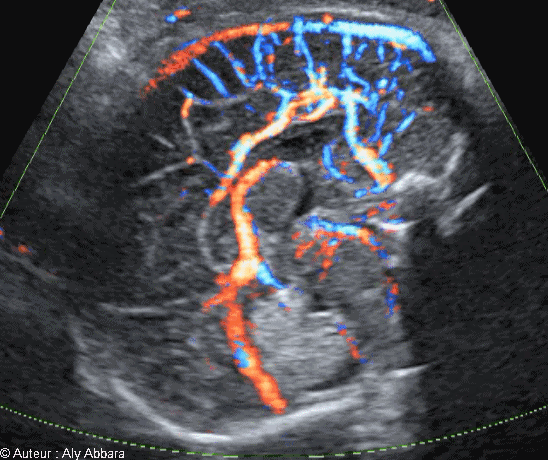

Image échographique animée montrant les vaisseaux sanguins et les structures anatomiques identifiables sur une coupe sagittale médiane stricte du cerveau foetal à 33 SA.

Auteur Dr Aly ABBARA